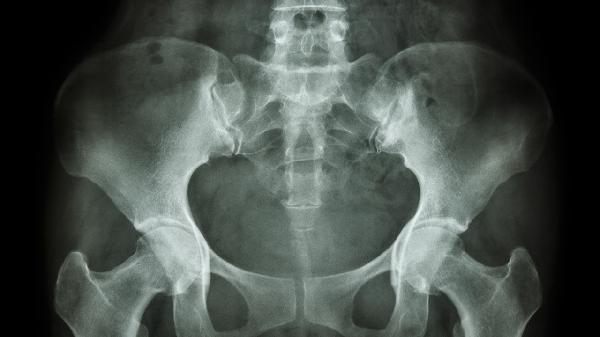

建议保持适度有氧运动增强骨盆稳定性,如游泳或瑜伽。避免提重物及穿高跟鞋,睡眠时在两膝间放置枕头减轻骨盆压力。若疼痛持续超过两周或伴随发热、排尿异常等症状,需及时进行骨盆X线、超声或CT检查明确病因。饮食注意增加奶制品、深绿色蔬菜等富含钙质食物摄入,控制咖啡因及碳酸饮料用量。